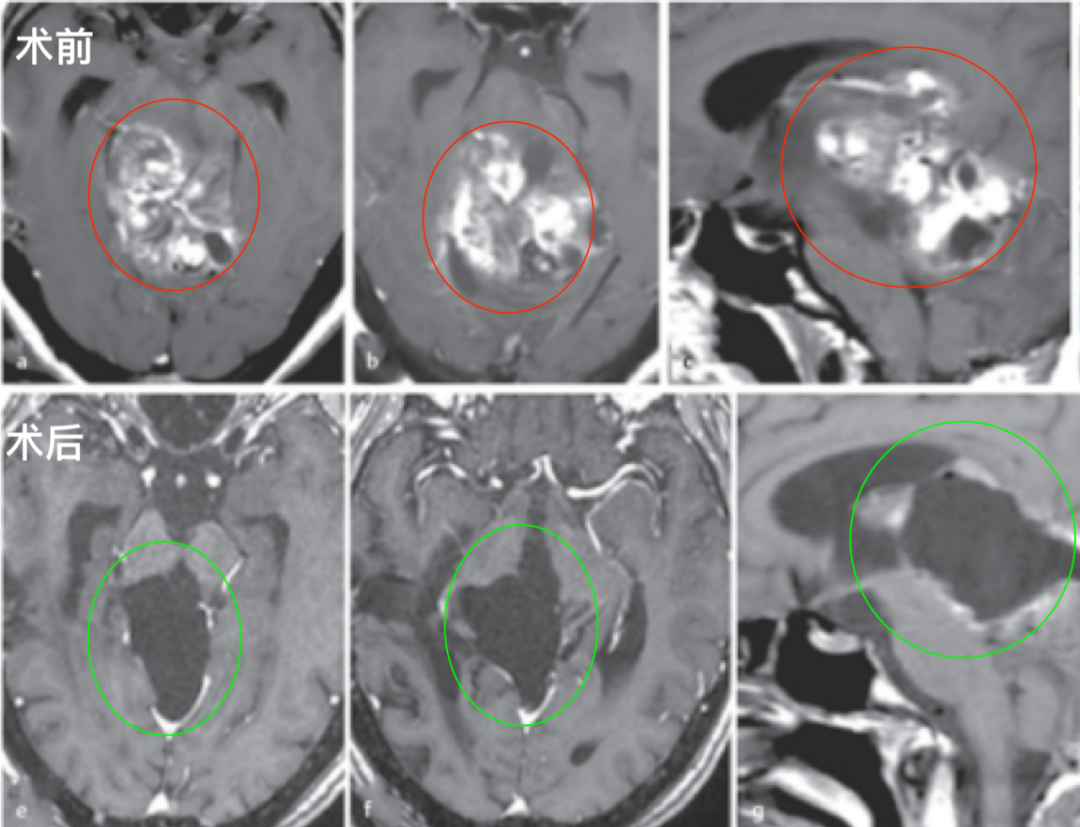

图:术前术后脑磁共振对比,巨大脑干胶质瘤全切,无神经脑组织损伤。

术后影像复查:毛细胞星形细胞瘤被成功切除。病人没有出现手术相关的神经功能损伤,随后的随访病程平安无事。

在肿瘤全切除术后10年的随访中,患者的病情持续良好,无肿瘤复发。